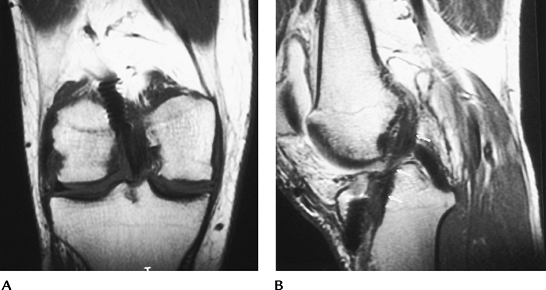

Osteonecrosis

Osteonecrosis (bone death) in the knee

Most cases are the result of systemic diseases, bone marrow disorders, or steroid therapy.

Spontaneous osteonecrosis of the knee is

(usually medial) that occurs in elderly or middle-aged patients,

Features of spontaneous osteonecrosis:

Pain, tenderness

Involves weight-bearing surface, unlike osteochondritis dissecans

Cause is likely related to subchondral insufficiency fracture

Leads to degenerative arthritis, loose bodies

Image features

Radiographs: osteonecrosis—subchondral sclerosis, fracture, articular collapse; infarction—peripheral calcification

Radionuclide scans: increased tracer

MRI: osteonecrosis—geographic zone of

infarction—serpiginous zone demarcating the margins of infarction

![]() |

FIGURE 5-59

P.283

FIGURE 5-60 Standing views of the knees demonstrating bilateral bone infarcts with dense ossification or calcification along the margins.

P.284

FIGURE 5-61 Coronal T1-weighted images of the knees with avascular necrosis in both femoral condyles and tibial and femoral bone infarcts.